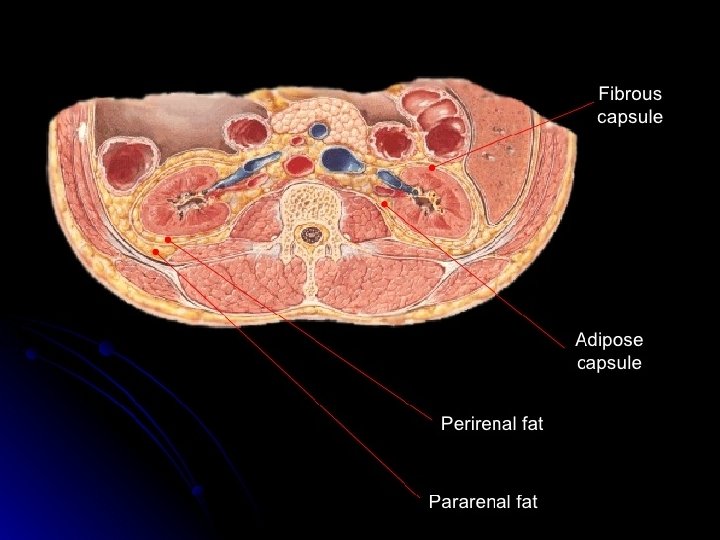

Floating kidney • The kidney is kept in position by the perirenal fat and renal fascia. However , each kidney moves up and down with respiration. If the amount of perinephric fat is reduced , the mobility of the kidney becomes excessive and may reduce the symptoms of the renal colic caused by the kinking of the ureter. A floating kidney can move up and down but not from the side to side within the renal fascia.